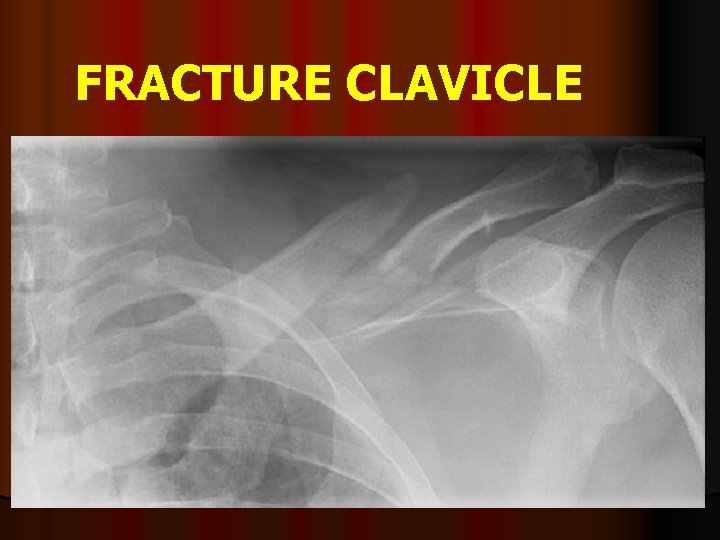

FRACTURE CLAVICLE